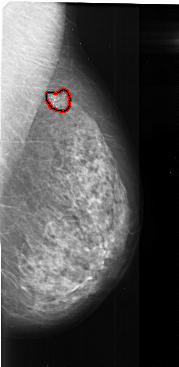

RIGHT_MLO LINES 5491 PIXELS_PER_LINE 2671 BITS_PER_PIXEL 16 RESOLUTION 42 OVERLAY

FILE: A_1023_1.RIGHT_MLO.OVERLAY

TOTAL_ABNORMALITIES 1

ABNORMALITY 1

LESION_TYPE CALCIFICATION TYPE FINE_LINEAR_BRANCHING DISTRIBUTION CLUSTERED

ASSESSMENT 5

SUBTLETY 5

PATHOLOGY MALIGNANT

TOTAL_OUTLINES 1

BOUNDARY